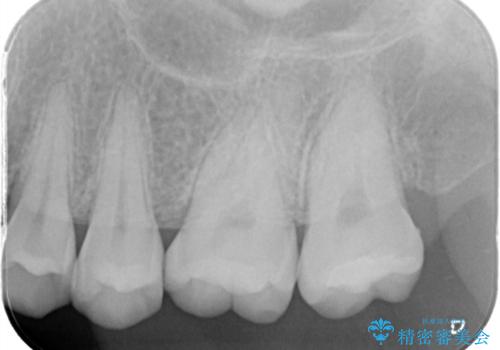

レントゲンから昔詰めた保険の詰め物が入っていることが確認できました。詰め物と歯の隙間が虫歯になっていたためしっかり取り除き、適合の良いセラミックインレーを入れました。